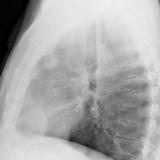

Case 9 Thymoma PA

Date: 04/04/2010

Views: 3182